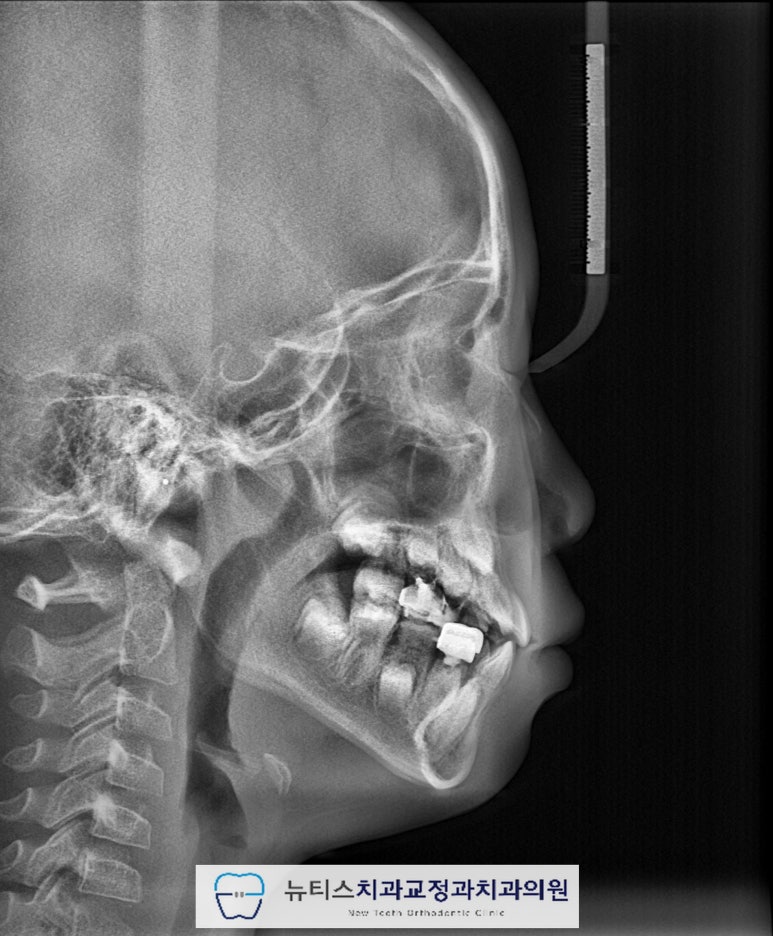

¾È³çÇϼ¼¿ä.ºÎ»ê ±ÝÁ¤±¸ ±¸¼µ¿¿¡ À§Ä¡ÇÑ´ºÆ¼½ºÄ¡°ú±³Á¤°ú Ä¡°úÀÇ¿ø±³Á¤°ú Àü¹®ÀǾȼö¹ü ¿øÀåÀÔ´Ï´Ù. À̹ø ÁÖºÎÅÍ À帶°¡ ½ÃÀ۵ȴٰí ÇÕ´Ï´Ù~Áö³ÁÖ¿¡µµ À帶°¡ ½ÃÀ۵ȴٰí ÇÏ´øµ¥...7¿ùÀº ÈÄ´þÁö±ÙÇÑ ³¯¾¾°¡ À̾îÁö³×¿ä. ÀϱⰡ º¯È¹«»óÇÏ´Ï´Ùµé °Ç° °ü¸® Àß ÇÏ½Ã±æ ¹Ù¶ø´Ï´Ù~ À̹ø¿¡ Æ÷½ºÆÃÇÒ ÄÉÀ̽º´Â"#ºÎ»ê¾î¸°À̹ݴ뱳ÇÕ ÀÔ´Ï´Ù. ¹Ý´ë±³ÇÕÀ» °¡Áö°í ÀÖÀ¸¸é Á¤»óÀûÀÎ ¼ºÀå ¹ßÀ°À» ÇÏÁö ¸øÇÏ¿©ÁÖ°ÆÅÎÀÌ ´õ ½ÉÇØÁú ¼ö ÀÖÀ¸¸ç ºÎÁ¤±³ÇÕÀÌ ¹ß»ýµË´Ï´Ù. ¼ºÀÎÀÇ °æ¿ì ½ÉÇÑ ¹Ý´ë±³ÇÕ Áï, ÁÖ°ÆÅÎÀº ±³Á¤Ä¡·á¸¸À¸·Î ÇØ°áÀÌ ¾î·Á¿ï ¼ö ÀÖÀ¸³ª ¼ºÀå±â ¾î¸°ÀÌÀÇ °æ¿ì¿¡´ÂÁ¤»óÀûÀÎ ¼ºÀå ¹æÇâÀ¸·Î À¯µµÇØ º¼ ¼ö ÀÖ½À´Ï´Ù. À̰¡ Ʋ¾îÁö°í µ¡´Ï°¡ Àְųª °ø°£ÀÌ ¸¹ÀÌ ÀÖ´Â °æ¿ì¿¡´Âº¸È£Àںв²¼ ÀÎÁö°¡ ºü¸£³ªÀÌ·± ºÎÁ¤±³ÇÕ (¹Ý´ë±³ÇÕ) À» °¡Áö°í ÀÖÀ¸¸é Àß ¸ð¸£½Ã´Â °æ¿ì°¡ ¸¹½À´Ï´Ù. ÈçÈ÷ ¾Þ±Û¾¾ 3±Þ ºÎÁ¤±³ÇÕÀ̶ó°í Çϴµ¥À̸¦ ¹æÄ¡ÇÏ°Ô µÇ¸é ³ªÁß¿¡ ¹®Á¦°¡ Å©°Ô µÉ ¼ö ÀÖÀ¸´Ï°¡±ÞÀû ºü¸¥ Á¢±ÙÀÌ ¿ä±¸µË´Ï´Ù.(¾ÆÀÌ º¸Çè¿¡¼ º¸ÀåÇØ ÁÖ´Â °æ¿ìµµ ÀÖ½À´Ï´Ù) #ºÎ»ê¾î¸°À̱³Á¤Ä¡°ú ÀÎ ÀúÈñ ´ºÆ¼½º¿¡¼´Â¼ö¿ÏºÎ (¼Õ»À) ¿¢½º·¹À̸¦ ÅëÇØ¿ì¸® ¾ÆÀÌÀÇ ¼ºÀå ´Ü°è¸¦ ÆÇ´ÜÇÏ¿© °¡Àå ÀûÀýÇÑ ½Ã±â¿¡ Ä¡·á¸¦ ÁøÇàÇÒ ¼ö ÀÖµµ·Ï ÇØ µå¸³´Ï´Ù. À̰¡ ¹Ý´ë·Î ¹°¸°´Ù°í ÇÏ¿©#ºÎ»ê¾î¸°À̱³Á¤Ä¡°ú ÀÎ ÀúÈñ ´ºÆ¼½º·Î³»¿øÇϽŠºÐÀÔ´Ï´Ù.ÃÊÁø »çÁøÀÔ´Ï´Ù.È¥ÇÕÄ¡¿±â ´Ü°è·Î ÇöÀç ¾Õ´Ï°¡ ¹Ý´ë·Î ¹°¸®°í ÀÖ½À´Ï´Ù. ÀÌ·¯ÇÑ #ºÎ»ê¾î¸°À̹ݴ뱳ÇÕ À» º¸ÀÌ´Â °æ¿ì¿¡´ÂÁ¤»óÀûÀÎ ÅÎÀÇ ¼ºÀåÀ» ÀúÇØÇÒ ¼ö ÀÖ½À´Ï´Ù. ¹æ»ç¼± »çÁø¿¡¼µµ¾Õ´ÏÀÇ ¹Ý´ë±³ÇÕÀ» È®ÀÎÇÒ ¼ö ÀÖ½À´Ï´Ù. #ºÎ»ê¾î¸°À̱³Á¤Ä¡°ú ÀÎ ÀúÈñ ´ºÆ¼½º¿¡¼´Â¿©·¯°¡Áö °Ë»ç¸¦ ÅëÇÏ¿© ÇÁ¸®¿Ã¼Ò¶ó´Â ÀåÄ¡¸¦ »ç¿ëÇÏ¿©#ºÎ»ê¾î¸°À̹ݴ뱳ÇÕ À» °³¼±Çϱâ·Î ÇÏ¿´½À´Ï´Ù.  Ä¡·á ÈÄ »çÁøÀÔ´Ï´Ù.